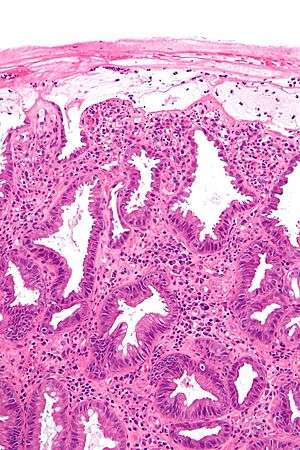

| Micrograph showing changes seen in ischemic colitis. H&E stain. | |

A range of pathologic findings are seen in ischemic colitis, corresponding to the spectrum of clinical severity. In its mildest form, mucosal and submucosal hemorrhage and edema are seen, possibly with mild necrosis or ulceration.[4] With more severe ischemia, a pathologic picture resembling inflammatory bowel disease (i.e. chronic ulcerations, crypt abscesses and pseudopolyps) may be seen.[20] In the most severe cases, transmural infarction with resulting perforation may be seen; after recovery, the muscularis propria may be replaced by fibrous tissue, resulting in a stricture.[4] Following restoration of normal blood flow, reperfusion injury may also contribute to the damage to the colon.[21]